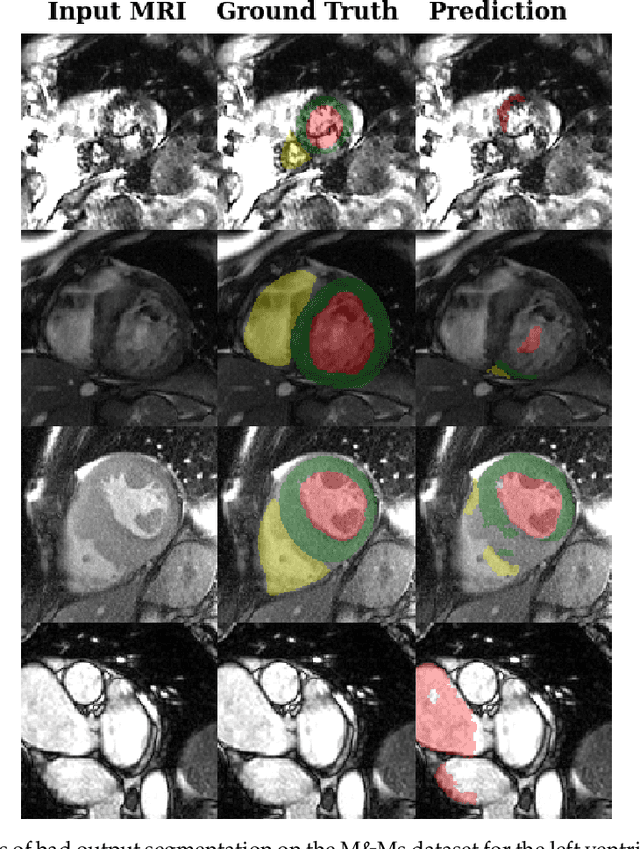

Deep learning methods are the de-facto solutions to a multitude of medical image analysis tasks. Cardiac MRI segmentation is one such application which, like many others, requires a large number of annotated data so a trained network can generalize well. Unfortunately, the process of having a large number of manually curated images by medical experts is both slow and utterly expensive. In this paper, we set out to explore whether expert knowledge is a strict requirement for the creation of annotated datasets that machine learning can successfully train on. To do so, we gauged the performance of three segmentation models, namely U-Net, Attention U-Net, and ENet, trained with different loss functions on expert and non-expert groundtruth for cardiac cine-MRI segmentation. Evaluation was done with classic segmentation metrics (Dice index and Hausdorff distance) as well as clinical measurements, such as the ventricular ejection fractions and the myocardial mass. Results reveal that generalization performances of a segmentation neural network trained on non-expert groundtruth data is, to all practical purposes, as good as on expert groundtruth data, in particular when the non-expert gets a decent level of training, highlighting an opportunity for the efficient and cheap creation of annotations for cardiac datasets.